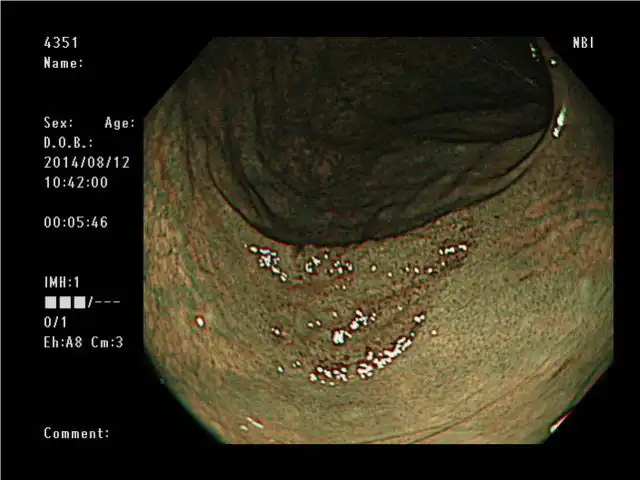

高清 和 NBI(窄带成像)

凭借其高清图像质量,PCF-H290ZL/I使粘膜表面清晰可见。与更明亮的NBI相结合,可增强粘膜组织和毛细血管网络,以进一步支持详细观察。

白光 NBI